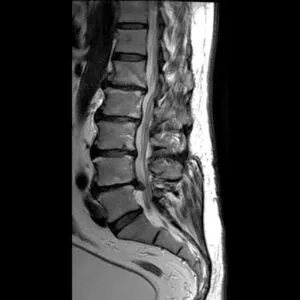

MRI

GE社製のSIGNA Creator 1.5T(テスラ)を導入しています。強力磁石と電波を使って体内の状態を鮮明に見ることができます。膝関節疾患を始めとする他の関節の疾患はもちろん、神経、筋肉・腱の異常や、腫瘍病変などの診断に有用です。

MRIで検査した画像